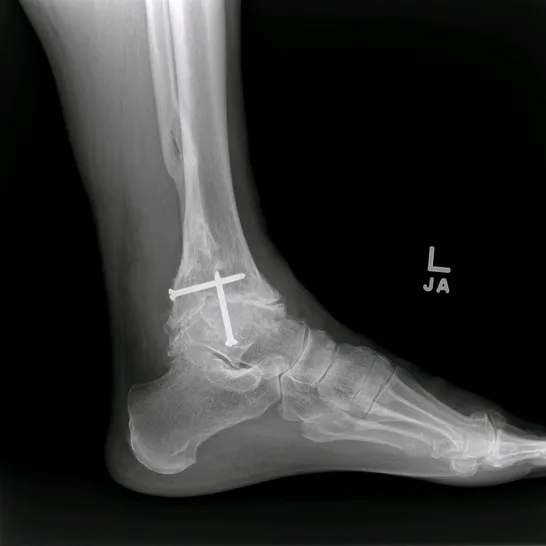

The following are images after surgical replacement of the ankle joint with a mobile bearing ankle prosthetic called the S.T.A.R. (SBI). This replacement joint will function similarly to a normal anatomical joint, allowing the patient normal function in daily activities, but was not designed to take repetitive use during more intense athletic activity. The joint has a polyethylene spacer between two metal parts that acts as shock absorber and gliding agent similar to cartilage. There is physical therapy that is required after surgical joint replacement in order to get the patient back to funcional capacity.

Pre and Post op Pics of Arthiitic Ankle S/P Total Ankle Replacement (TAR)

Preop, Intraop and Postop X-rays status post Total Ankle Replacement for Ankle Arthritis